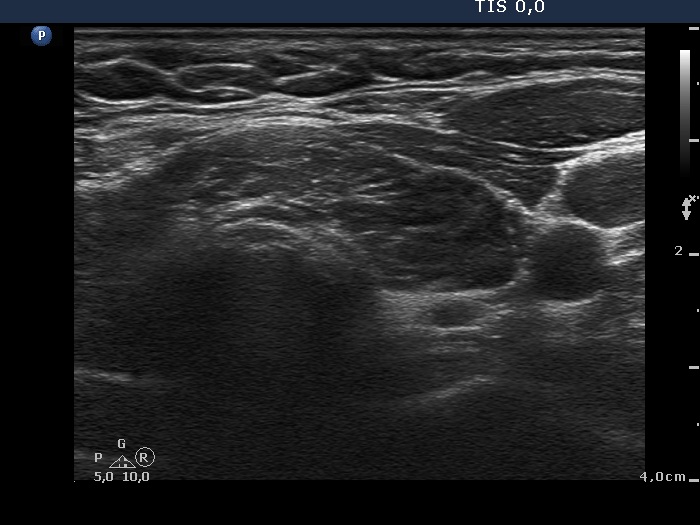

Discrete lesion or nodule in Hashimoto's thyroiditis - case 16 (797) (ultrasonographic picture 3)

Isthmus and lower part of the left lobe, transverse view. Note the synchronous presence of echogenic granules and lines; this pattern corresponds to connective tissue.